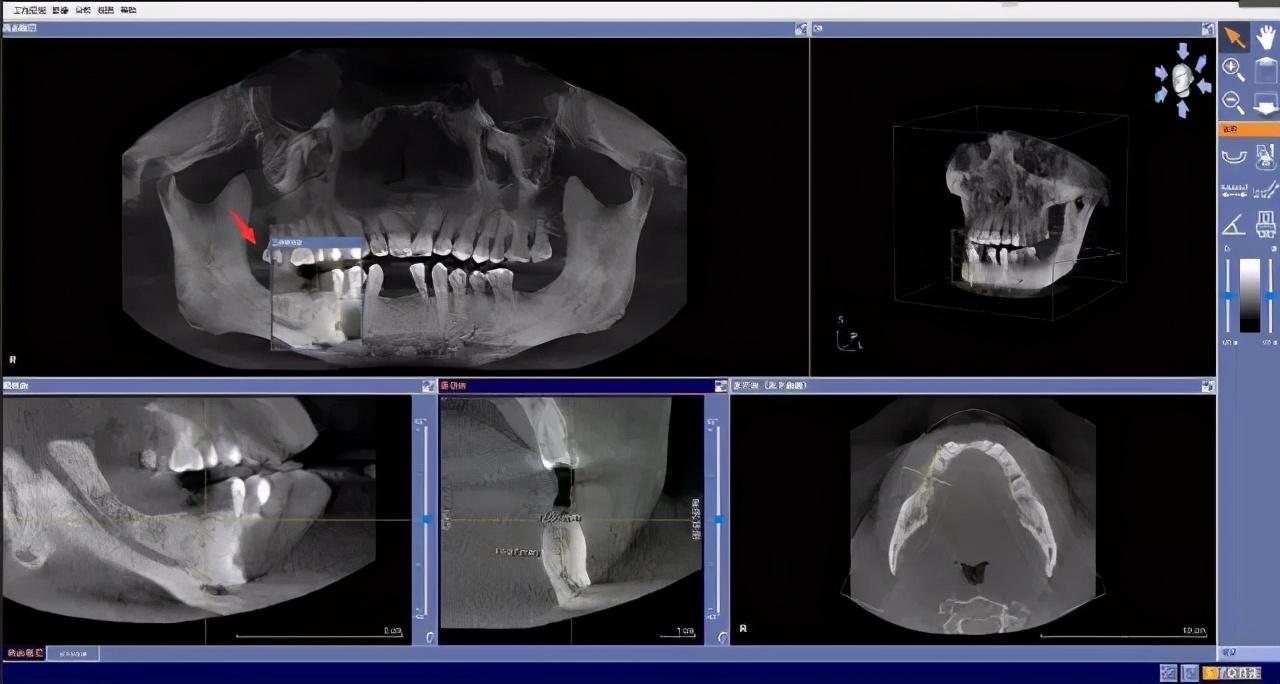

先要做一個(gè)口腔全景片、頜骨CT等

醫(yī)生根據(jù)機(jī)器成像查看口腔的具體情況,

是否有炎癥、牙槽骨的密度、吸收狀況

以及鄰牙組織、牙體組織等。

注明:此數(shù)據(jù)僅作模擬,不是確切種植數(shù)據(jù)。

如果僅靠雙眼大致估測(cè)口內(nèi)數(shù)據(jù),是無法得到的高度、寬度的,也無法確認(rèn)骨頭吸收多少,是否需要植入骨粉。

對(duì)后期手術(shù)有一定的影響。

通過全景片可以“解剖”牙齒測(cè)量,適宜的種植角度也可確定,健康有保障。